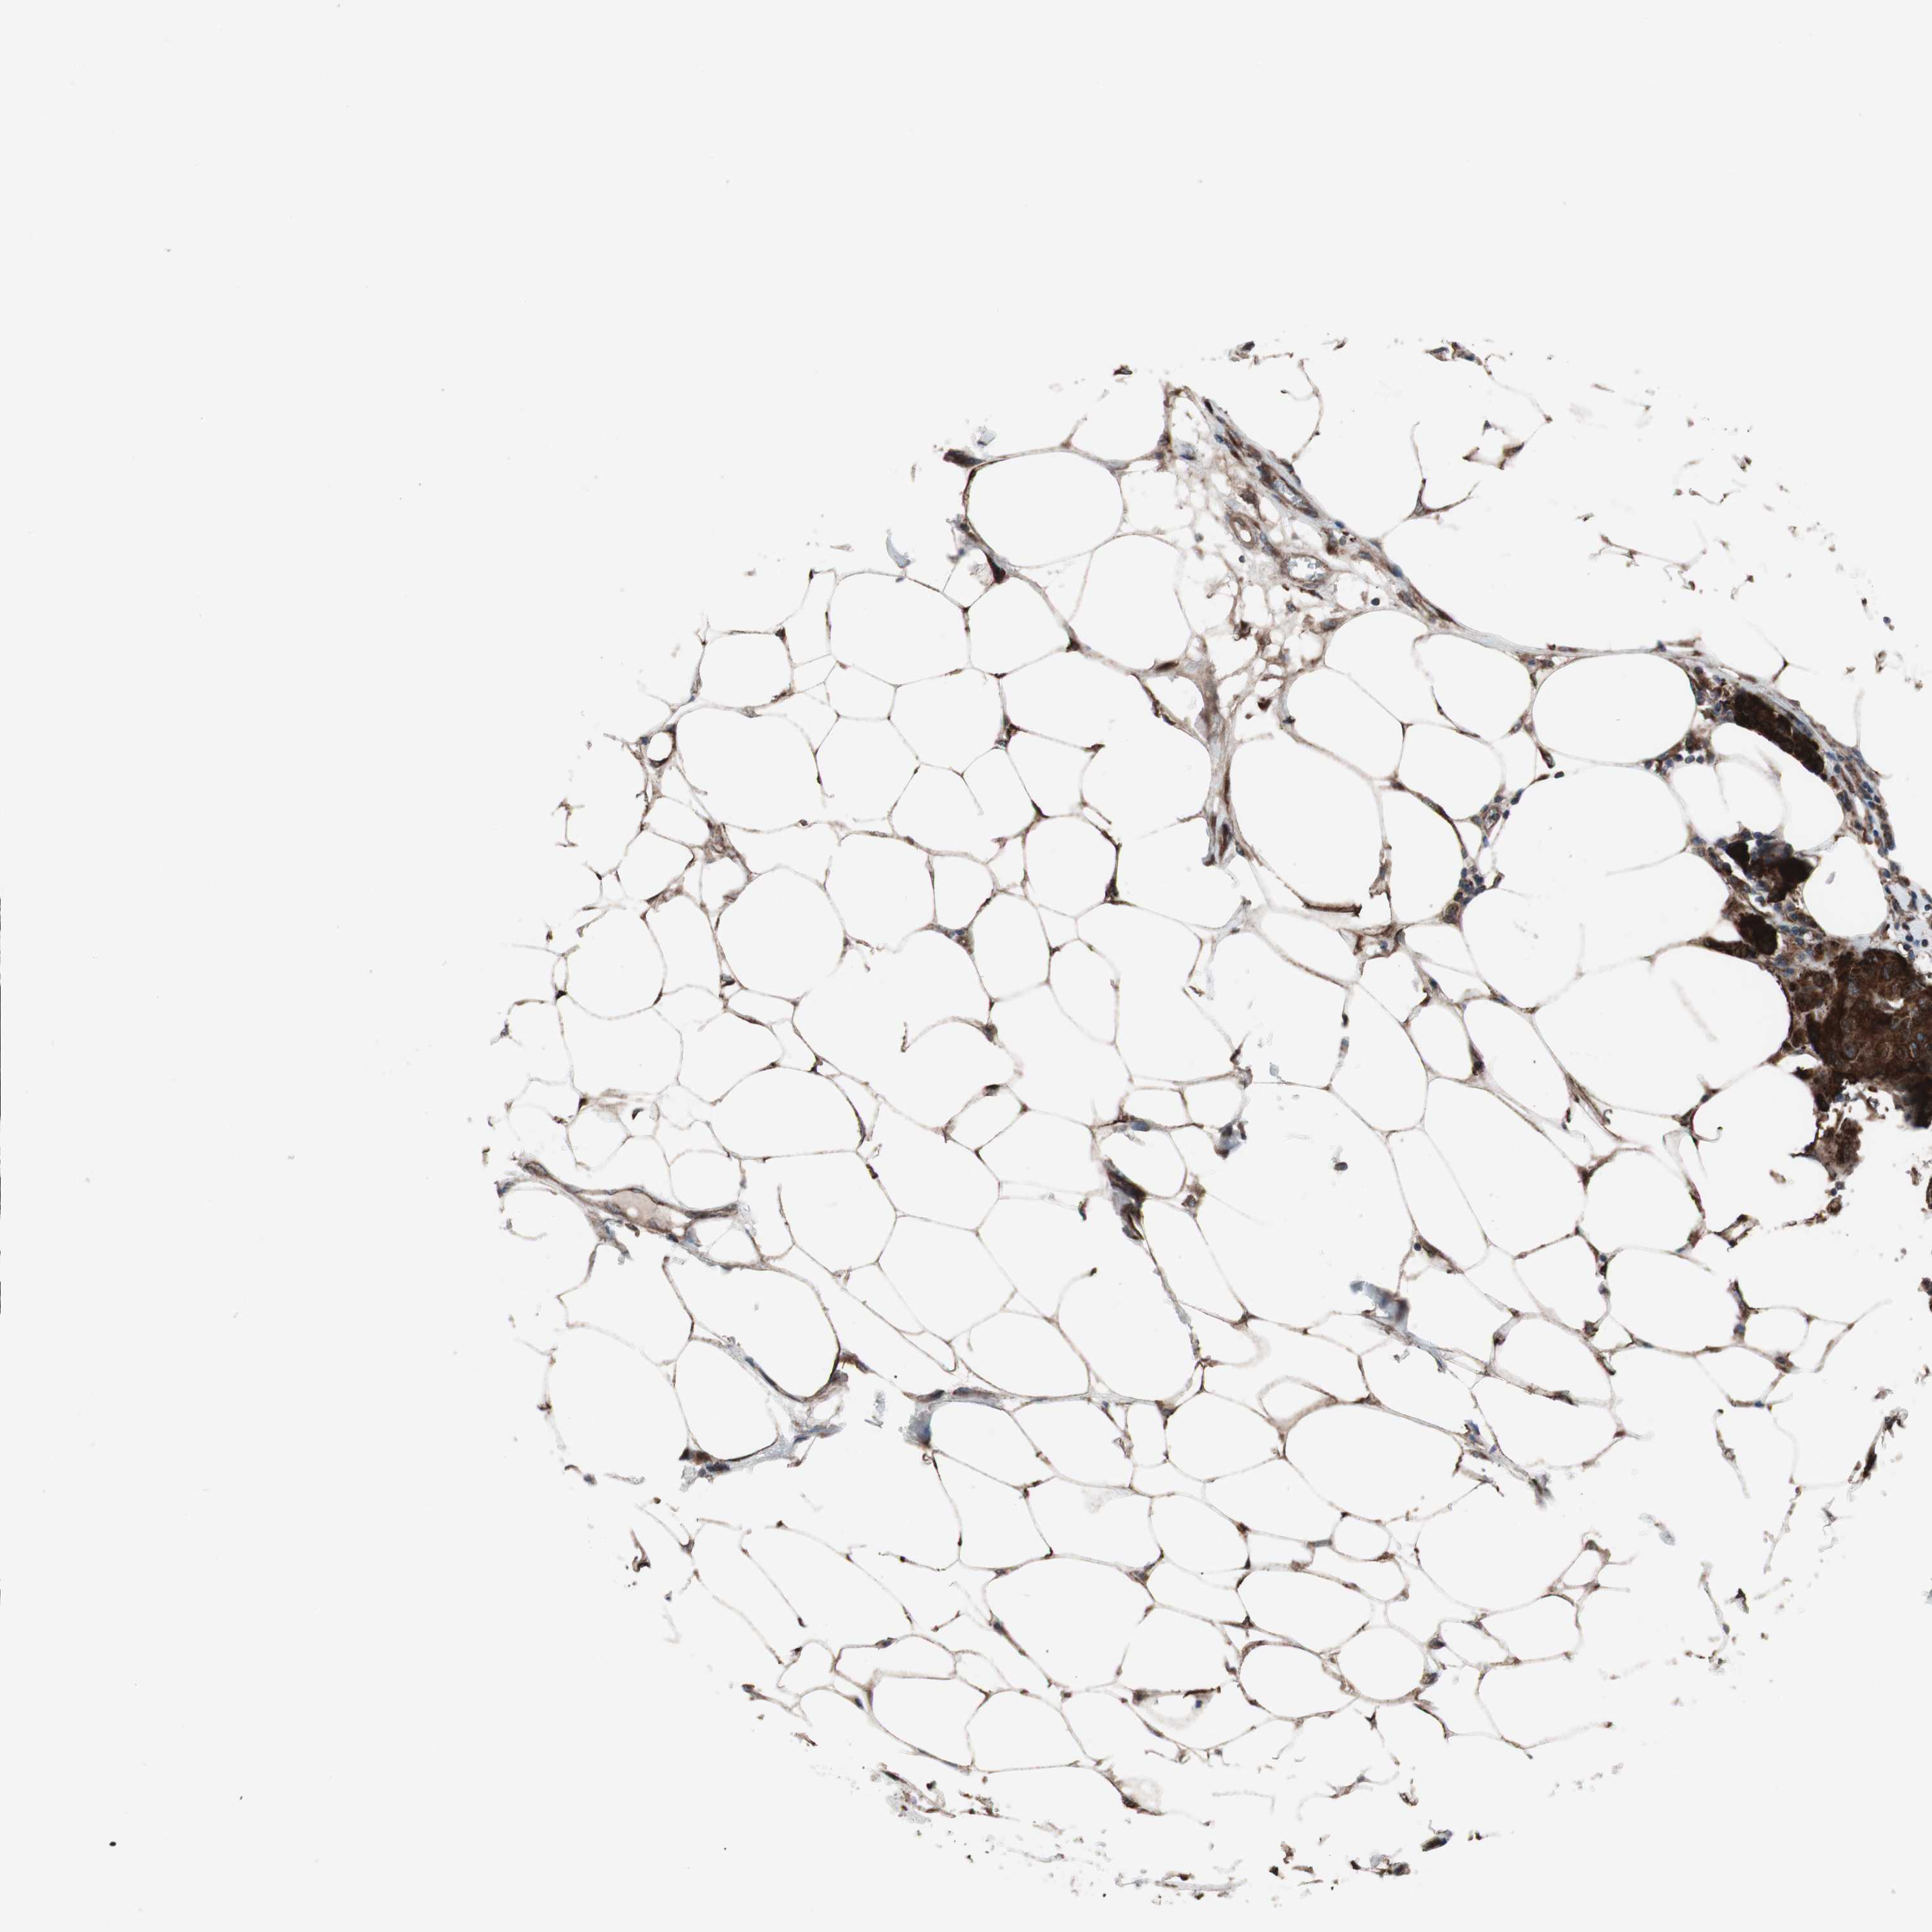

CANCER BREAST CANCER Show tissue menu

BRCA TCGA BRCA VALIDATION PROTEIN EXPRESSION